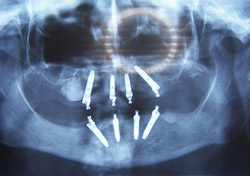

Metoda nazvana "All-on-4" („Sve-na-4"), "All-on-6" („Sve-na-6") u mnogočemu je revolucionarna. Implantološka metoda „All on 4”(„Sve na 4”) je rješenje za bezubu čeljust, gdje se umjesto totalne proteze izrađuje cirkularni hibridni most samo nad 4 implantata. Inače bi takav most trebalo nositi 6-8 implantata. Most je za implantate pričvršćen malim vijcima te se može skinuti u slučaju potrebe.

"All-on-6"

U bezubu čeljust postavlja se 6 implantata u koje se zavida takozvani hibridni most koji nadomješta zube i resorbirani greben.